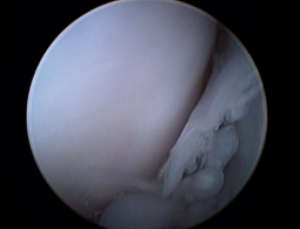

半月板の関節鏡評価

(左上)正常半月板 (右上)半月板損傷 バケツの取っ手型損傷 典型的な犬の半月板損傷の形態 (左下)半月板損傷 フラップ型 (右下)半月板損傷部を検査棒で引き出しているところ